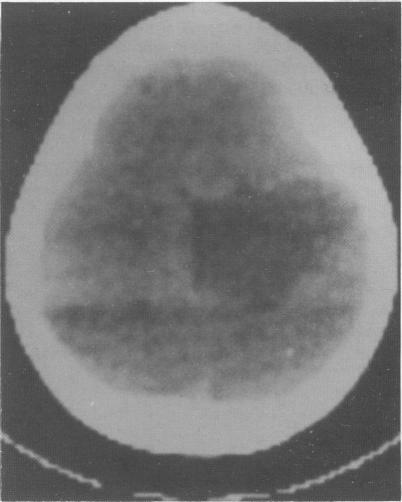

We studied eight patients with indolent gliomas. In all eight cases, despite characteristic radiological features, there was a delay in diagnosis because of misinterpretation of the initial computed tomogram. These tumours are an important cause of epilepsy of childhood, and surgery may well alleviate the epilepsy and possibly achieve a long term 'cure'. Therefore it is important that a diagnosis is made early and the lesion completely excised.